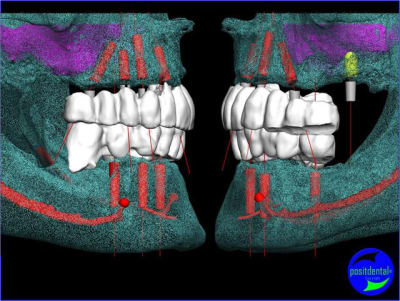

projet implantaire pour février

1er étape le wax-Up, dans ce cas clinique il est réalisé en 3D

> 2 ANS après MCI Bimaxillaire en 1 intervantion

Depuis + de 10 ans Positdental a développé des solutions technique pour indexer le pilier prothétiques lorsque l'implant est angulé, une des réalisations en 2008.